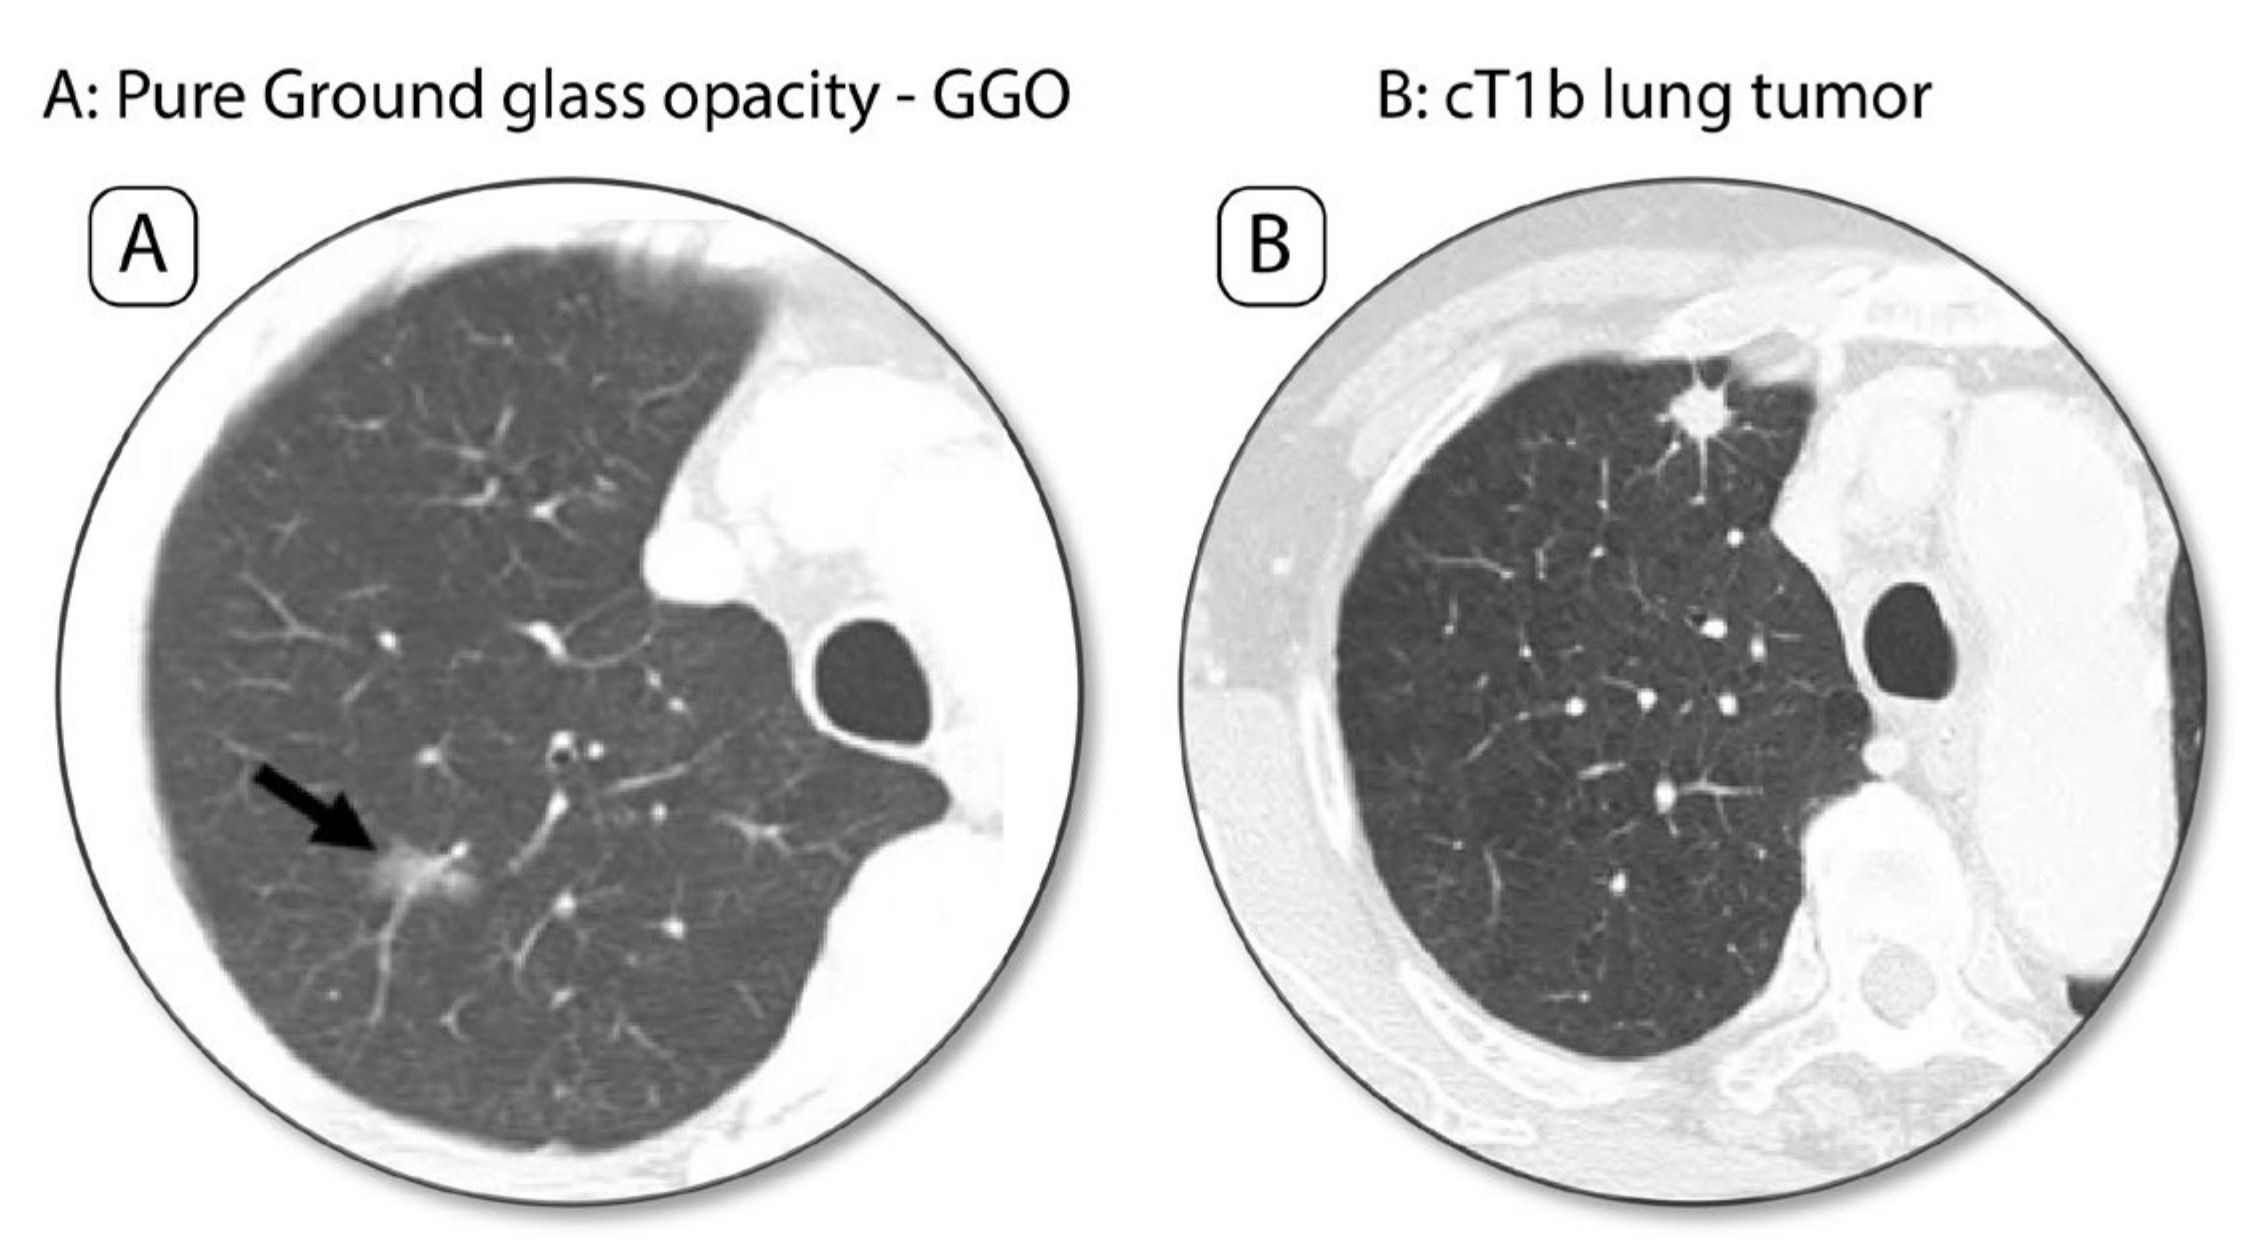

3.2.2. “Resecting Less”, Segmentectomy for Early-Stage NSCLC, from Present to Future